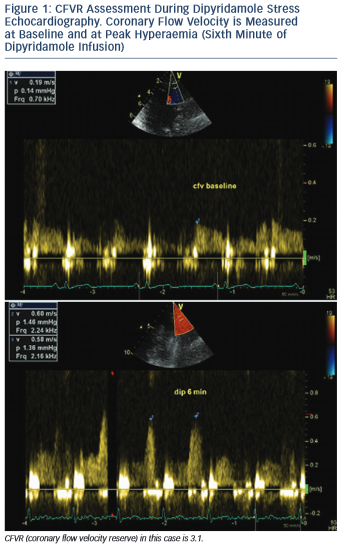

Coronary flow velocity reserve (CFVR) represents the ratio between maximal (stimulated) coronary blood flow, induced by using a coronary vasodilator, and baseline (resting) blood flow (see Figure 1). As a ratio it is a dimensionless variable. It could be measured with different tools – some of them, such as intracoronary Doppler flow wire and coronary sinus thermodilution, are invasive methods and therefore associated with certain risks, radiation exposure, increased cost and ethical considerations.1 Other methods, such as cardiac magnetic resonance imaging and cardiac nuclear imaging, are non-invasive and useful for clinical research, but with limited clinical application because they are complex, time-consuming, with limited availability and expensive.2,3